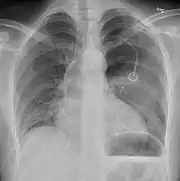

Chest X-ray

A plain chest radiograph, ideally with the X-ray beams being projected from the back (posteroanterior, or "PA"), and during maximal inspiration (holding one's breath), is the most appropriate first investigation.[30] It is not believed that routinely taking images during expiration would confer any benefit.[31] Still, they may be useful in the detection of a pneumothorax when clinical suspicion is high but yet an inspiratory radiograph appears normal.[32] Also, if the PA X-ray does not show a pneumothorax but there is a strong suspicion of one, lateral X-rays (with beams projecting from the side) may be performed, but this is not routine practice.[15][19]

The size of the pneumothorax (i.e. the volume of air in the pleural space) can be determined with a reasonable degree of accuracy by measuring the distance between the chest wall and the lung. This is relevant to treatment, as smaller pneumothoraces may be managed differently. An air rim of 2 cm means that the pneumothorax occupies about 50% of the hemithorax.[15] British professional guidelines have traditionally stated that the measurement should be performed at the level of the hilum (where blood vessels and airways enter the lung) with 2 cm as the cutoff,[15] while American guidelines state that the measurement should be done at the apex (top) of the lung with 3 cm differentiating between a "small" and a "large" pneumothorax.[33] The latter method may overestimate the size of a pneumothorax if it is located mainly at the apex, which is a common occurrence.[15] The various methods correlate poorly but are the best easily available ways of estimating pneumothorax size.[15][19] CT scanning (see below) can provide a more accurate determination of the size of the pneumothorax, but its routine use in this setting is not recommended.[33]

Not all pneumothoraces are uniform; some only form a pocket of air in a particular place in the chest.[15] Small amounts of fluid may be noted on the chest X-ray (hydropneumothorax); this may be blood (hemopneumothorax).[13] In some cases, the only significant abnormality may be the "deep sulcus sign", in which the normally small space between the chest wall and the diaphragm appears enlarged due to the abnormal presence of fluid.[16]